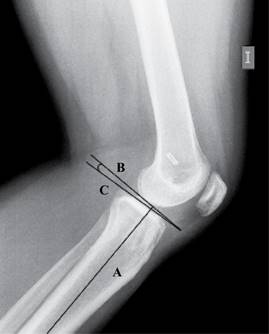

Para la medición del slope tibial, ésta se realizó en radiografías laterales de rodilla donde se trazó una primera línea en el eje de la diáfisis de la tibia (A), una segunda línea tangencial a la superficie de las mesetas tibiales (B) y una tercera línea (C) perpendicular a la línea A en el sitio de intersección AB. El ángulo formado por la línea B y C se considera como el valor del slope tibial (Figura 1).

La medición del slope tibial en nuestro estudio se realizó en radiografías laterales de rodilla tomando una medición técnicamente sencilla, por lo que consideramos que es un estudio radiográfico accesible para su reproducibilidad así como de fácil medición con la técnica mencionada anteriormente (Figura 1). Existen otros estudios en los que se valora la medición del slope tibial medial y lateral en tomografía axial computarizada,9 que revelan una mayor relación entre el slope tibial lateral y la falla del injerto;13 sin embargo, son estudios de mayor costo y dificultad en su toma a diferencia de la radiografía simple que fue usada en nuestro estudio.